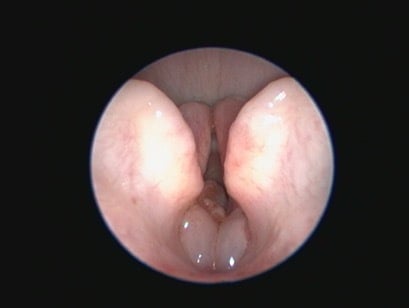

Traditional surgical treatment has largely focused on staphylectomy (soft palate resection) and rhinoplasty (nostril wedge resection). The value of laryngeal saccule excision has been debated, but overall is probably more widely performed than not (Figure 3). With increased availability of advanced imaging modalities and data from WBBP-based research, modifications of multilevel surgery (MLS) with a better outcome compared to traditional surgery include a modified folding flap palatoplasty (Figure 4), rostral alar fold resection and modified alar wing resection (Liu et al., 2017). Depending on the individual patient findings, tonsillectomy and laryngeal procedures (eg resection of everted laryngeal saccules, partial cuneiform arytenoidectomy) may also be indicated. Laser-assisted turbinectomy (LATE) can benefit some dogs, although currently in the UK this would generally be a later surgical procedure performed in refractory animals that may require some concurrent revision of the original MLS procedures. Age, body condition and laryngeal collapse have been found to be the main prognostic indicators for surgery – younger dogs, normal/underweight dogs and those with laryngeal collapse (worse than everted laryngeal saccules) have a poorer prognosis (Liu et al., 2017).